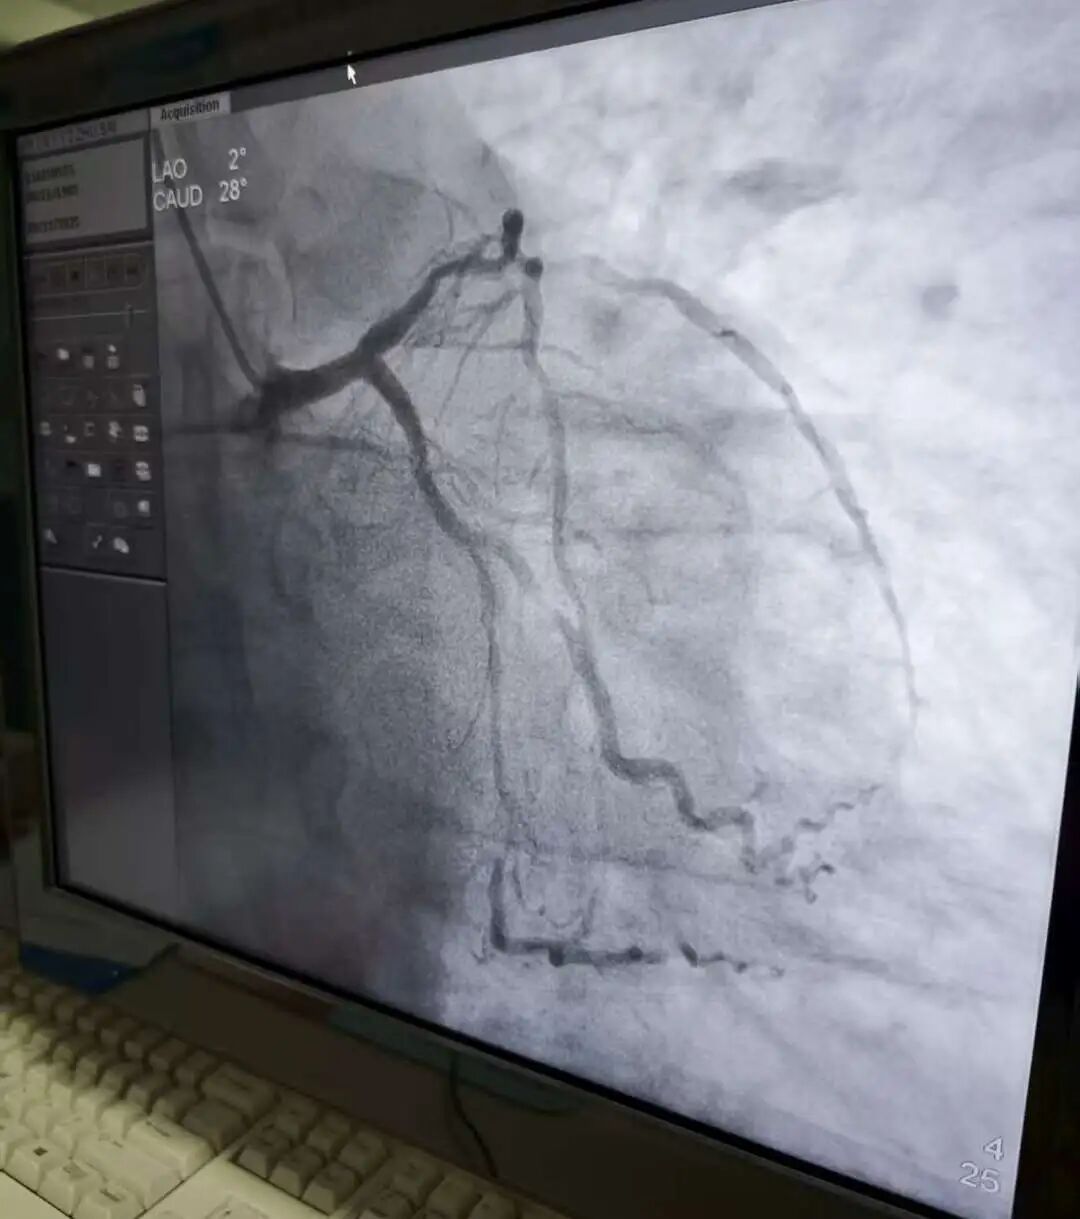

一名急性前间壁心肌梗死患者紧急入院,面色苍白、大汗淋漓。翻越海拔4000多米的高山,转运至上级医院需近9小时车程——时间就是心肌,时间就是生命!

危急时刻,方一鸣与王天游等援川医护人员迅速响应,协同急诊科当班医生张艳宏完善检查、精准评估,果断启动溶栓治疗方案。护士团队娴熟建立静脉通路,药物缓缓注入患者体内……症状逐渐缓解,生命体征趋于平稳。

与此同时,急救团队已提前联络甘孜州人民医院心内科,开通绿色通道。次日上午11时,患者顺利转诊;中午12点,PCI手术顺利完成,成功脱险!